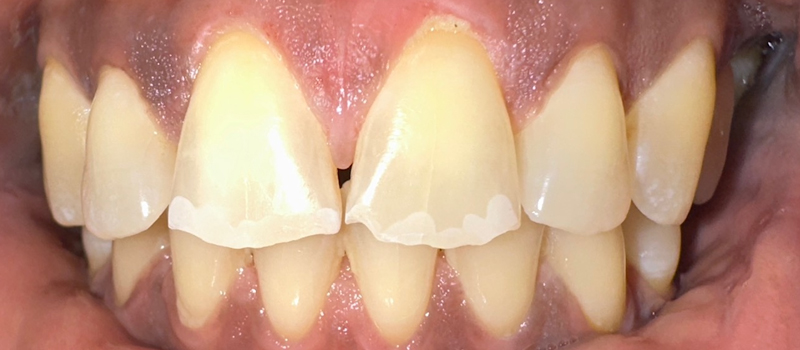

The doctor recommended a deep cleaning (scaling and root planing) to treat the infection below my gums. When they showed me before and after photos from my teeth, I was shocked! The difference was incredible—I couldn’t believe how much healthier the gums looked after treatment. It opened my eyes.

Before